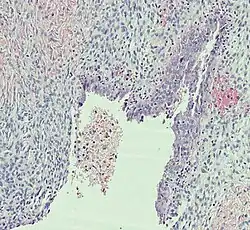

| Endometriosis | At least two of the following three criteria:[28]

|

| |